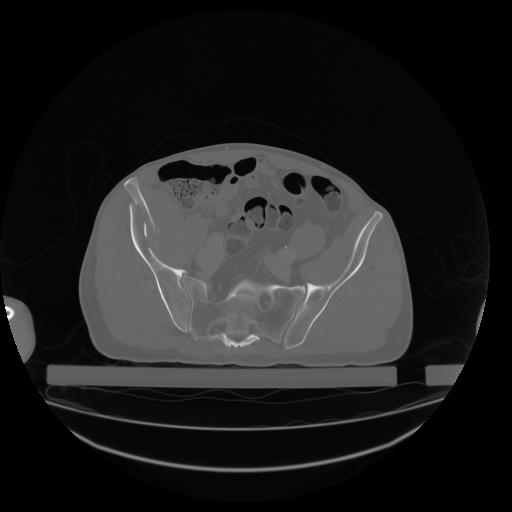

27 CUERPO,CE,Axial,3.0,CUERPO,,